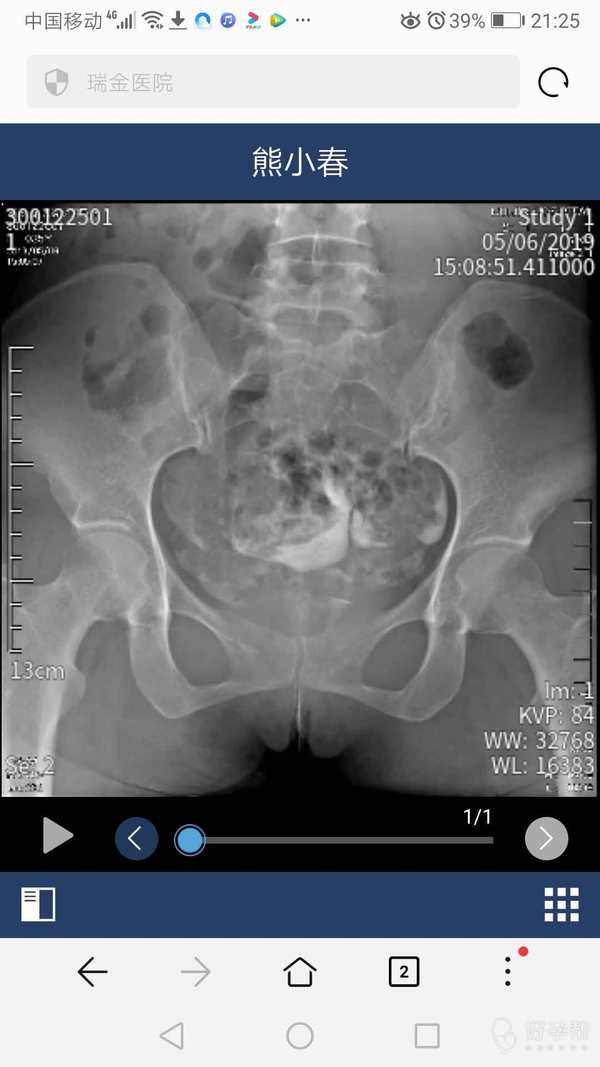

通而不畅,帮我看下怎么办,双子宫